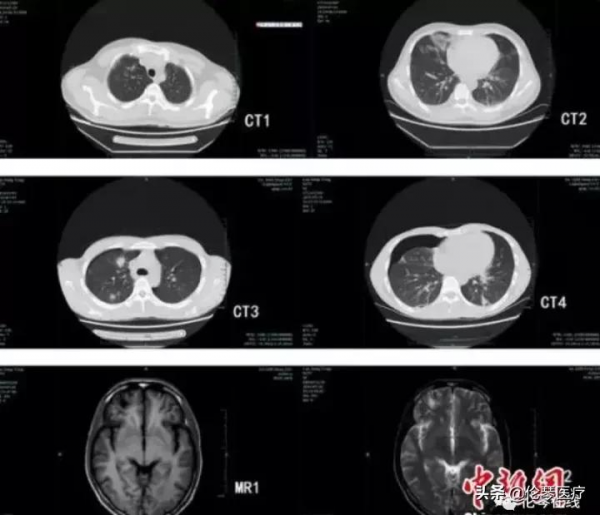

肺吸蟲亦可以侵犯肺部及胸膜,CT表現與病理三期相對應:

1、組織破壞期(膿腫期或侵潤期),蟲體在人體肺組織中移行引起線狀出血灶或隧道狀機械損傷。CT表現為邊緣模糊的斑片狀陰影,密度不均,而且因蟲體的移行,病灶部位隨之改變。並可見斑片影之間出現“隧道”徵表現。

2、組織反應期(囊腫期),蟲體分泌和代謝產物導致組織炎性反應變態反應性炎症。區域性組織壞死,周圍肉芽組織增生,並逐漸纖維化形成囊壁,即所謂的“並殖囊腫”。CT表現為結節團塊狀影為主,合併單囊或成簇穴窟狀多房囊狀改變。邊界較清,偶見條索影相連。

3、纖維瘢痕期,並殖囊腫內的蟲體死亡或移往別處,囊腫內及周邊的肉芽組織和纖維取代,形成瘢痕。CT表現為囊腫逐漸吸收,周圍紊亂的纖維條索或結節找,隨訪無變化。偶可見鈣化。胸膜侵犯亦很常見,胸膜增厚,特別是常見侷限性胸膜增厚。胸腔積液甚至早於肺內改變。具有特徵性的表現是雙側胸腔交替性積液,即一側胸水減少或吸收後出現對側胸水,少數病例有多次交替或同時出現胸水。心包增厚或心包少量積液亦可見。

右肺多發囊狀、穴窟樣低密度影和小片狀滲出

多發空洞,呈“隧道徵”

雙肺斑片狀滲出,並可見小囊狀影